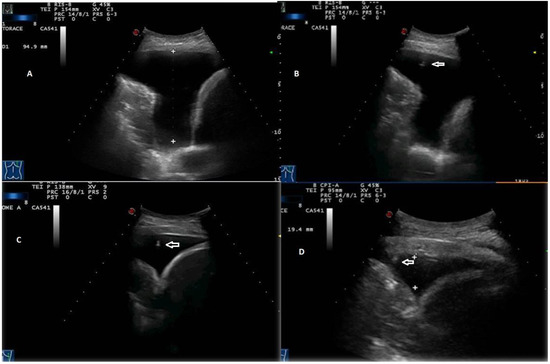

Figure 7. Stages of TUS-assisted thoracentesis. (A) Initial pleural effusion’s measurement using a convex 3.5 MHz holed probe. (BD) Progressive lung re-expansion during drainage. The position of the needle tip (white arrows) is highlighted during all phases of the procedure until the needle is retracted.

Third, the real-time TUS B-mode scans made it possible to monitor the reduction of the pleural fluid content during drainage, allowing the needle to be retracted as the lung parenchyma returned to the wall and until its removal after complete lung rehabilitation (Figure 7).